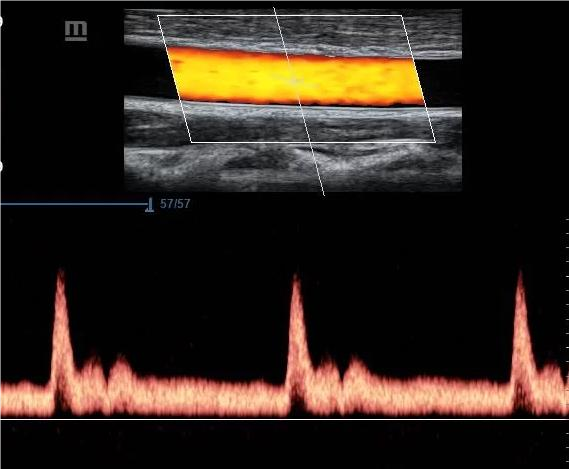

Доплеровата сонография е неинвазивен, безвреден и безболезнен  ултразвуков метод за перкутанно измерване на скоростта на кръвния ток в артериалните и венозните съдове. Основава се на доплеровия принцип, описан от австрийския физик Cristian Dopler през 1842г. Доплеровият ефект представлява промяна в честотата на подаваната и отразената от движещите се елементи ултразвукова емисия , наречена доплерова честотна разлика. Ултразвукът е звук с честота от  20 000 до 10 9 Hz.

• Дуплекс-сканиране-/В-сканиране в реално време и пулсова дирекционна доплерова сонография/-едновременно се регистрира скоростта на кръвния ток и се визуализира съдовата морфология.

• Триплекс-сканиране – комбинация от цветно дуплекс сканиране  в реално време с мощностен доплеров анализ със или без М-mode изобразяване.